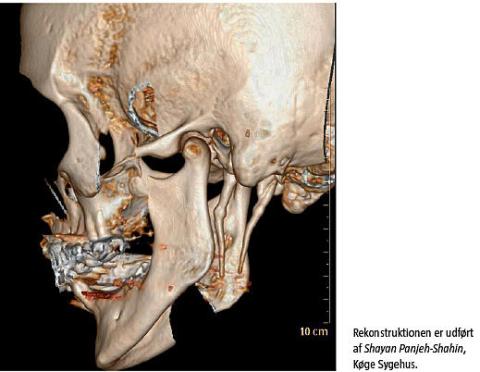

En 78-årig kvinde blev henvist pga. smerter i venstre side af halsen igennem 5-6 år. Patienten følte, at venstre side af tungen fyldte mere end højre side, hvilket bevirkede, at hun bed sig i tungen. Det eneste objektive fund var ømhed af venstre tonsilleje ved palpation. Ved tonsillejet kunne processus styloideus (PS) palperes foran den venstre tonsil. Ved en computertomografi (CT) af hoved og hals fandt man en forlænget PS. Den målte venstresidigt 52 mm og højresidigt 45 mm, og på den venstre side havde den en mere medial retning. Diagnosen Eagles syndrom (ES) blev stillet. Patienten afslog tilbud om operation, da hendes symptomer ikke generede hende i en sådan grad, at hun ønskede operation.

ES [1] er en tilstand med forlænget PS eller mineralisering af stylohyoideus eller af de stylomandibulære ligamenter. PS er sjældent over 30 mm, længden varierer dog fra 15,2 mm til 47,7 mm [2]. Man bør få mistanke om ES ved uforklarlige halssmerter og ømhed ved palpation af tonsillejet. Andre symptomer kan være øre- og halssmerter samt transitorisk cerebral iskæmi ved hoveddrejning på grund af den tætte relation til karskeden og kranienerverne. Diagnosen stilles ved CT af hoved og hals. Operationen foretages via en transkutan eller transoral adgang, hvor man fjerner den forlængede knogle. Symptomerne forsvinder ofte helt efter operationen [2].